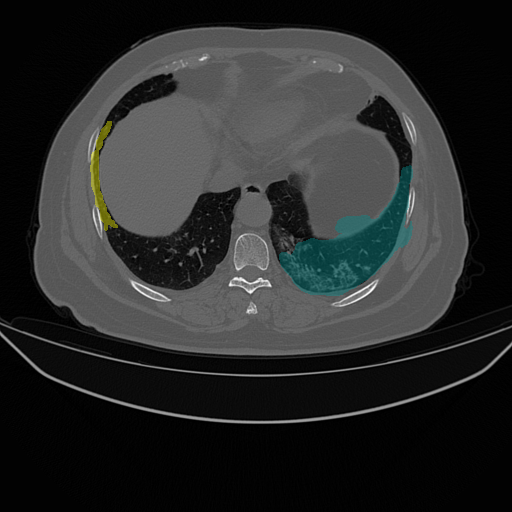

| Lung Segmentation (COV, 2019) Left lung (Cyan) Right lung (Yellow) | ![]() |

| (e) CT slice | (f) FGSM | (g) PGD | (h) Ours | |

While recent studies of adversarial attacks mainly focus on natural images, the research of adversarial attacks in the medical image domain is desired as there are significant differences between two domains. Beyond regular RGB cameras, there are various types of medical imaging equipments (e.g., Computed Tomography (CT) scanners, ultrasound transducers and fundus cameras) to generate dramatically different images. Fig. 1 shows three examples where an image captured from fundus camera is in (a), an image captured from the CT scanner is in (e) and an endoscopic video frame is in (i). As can be seen in the figure that these three images have little in common. The huge data variance across different modalities of medical images brings more challenges to develop a technology that works for all the modalities. In addition, existing investigations on medical adversarial attacks are limited. In Finlayson et al. (2019), adversarial examples are shown to deteriorate the diagnosis accuracy of deep learning based medical systems. These medical attack methods are mainly based on those from natural images (e.g., Fast Gradient Sign Method (FGSM) (Goodfellow et al., 2014) and Project Gradient Descent (PGD) (Madry et al., 2017), which are insufficiently developed for different types of medical data. As shown in Fig. 1, the adversarial examples generated by FGSM and PGD do not consistently decrease the network’s performance in (b), (c), (f), (g), (j) and (k). The data variance in (a) and (e) leads to the inconsistent attack results by existing methods.

We evaluate the proposed method on three medical image analysis tasks including diabetic retinopathy grading, artefact detection, and lung segmentation. The diabetic retinopathy grading is to classify fundus images into predefined categories for diabetes status estimation. The artefact detection is to detect specific artefacts like pixel saturations, motion blur, and specular reflections in the endoscopic images. Lung segmentation is to segment lung region from the whole CT slice. The medical data in one task is significantly different from that in others.

We use two datasets for diabetic retinopathy grading. One is the APTOS-2019 (APT, 2019) dataset with 3,662 fundus images. The other is a large-scale Kaggle-DR (Kag, 2015) dataset where we randomly select 11,000 fundus images from its original training set. Both APTOS-2019 and Kaggle-DR contains five defined categories. For artefact detection we use EAD-2019 (EAD, 2019) dataset with 2,500 images collected from endoscopic video frames and annotated artefact regions with seven defined categories. These detection images focus on multiple image modalities (i.e., gastroscopy, cystoscopy, gastro-oesophageal and colonoscopy), and are captured in multi-resolution with multi-modal (i.e., white light, fluorescence, and narrow band imaging). For lung segmentation, we use the COVID-19 dataset (COV, 2019) where there are 20 CT scans for lungs infected by COVID-19.